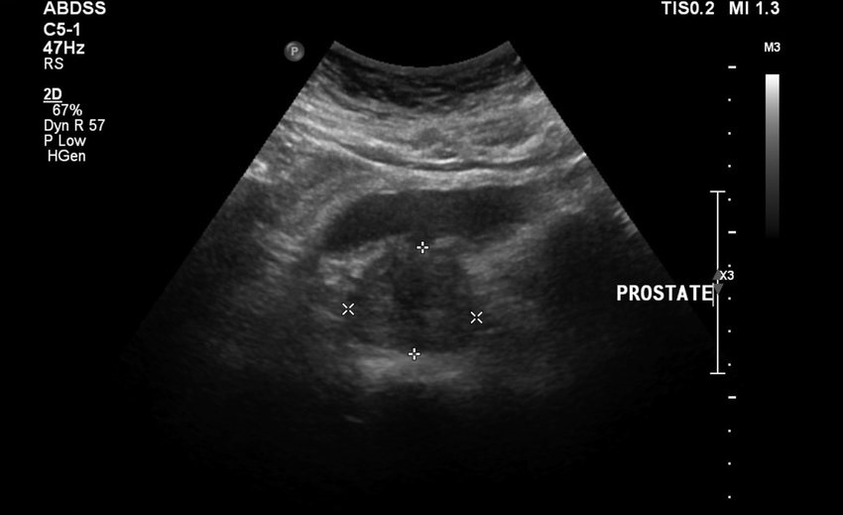

They did not let the rubber live, and then added lower back pain, and the tests and ultrasound results were not good.Literally, it is impossible to leave the toilet, the groin and the feeling of constant pain is heavy.Direct massage of the prostate was prescribed, which made me panic.He began to look for other less trauma-free healing methods.